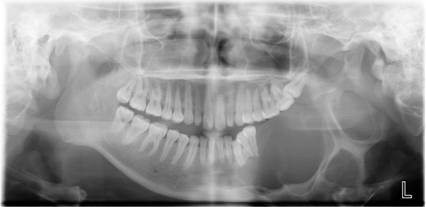

数字化口腔曲面体层片

诊断范围涉及牙体牙髓病、牙周病、阻生牙/多生牙定位、种植牙术前CT评估分析、颞下颌关节CT诊断分析、,颌骨及涎腺疾病、颌面发育畸形、正畸治疗辅助诊断等大部分颌面部疾病,为临床医疗提供强有力的支持。